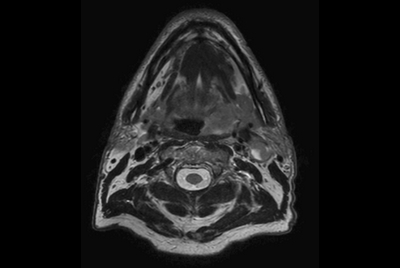

Soft Tissue of the neck